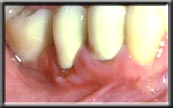

Some people are born without sufficient attached gingiva to prevent the muscle in the alveolar mucosa from pulling the gum down. In these cases the gum slowly continues to recede over time, even though the patient may be very conscientious with their oral health. This is not an infection, as is seen with periodontal disease, but rather simply an anatomic condition. Unfortunately, bone recession is occurring at the same time the gum is receding. This is because the bone, which is just under the gum, will not allow itself to become exposed to the oral cavity and moves down with the gum.

A lack of attached gingiva is sometimes associated with a high frenum attachment, which exaggerates the pull on the gum margin. A frenum is a naturally occurring muscle attachment, normally seen between the front teeth (either upper or lower). It is normal to have a frenum, but it should not pull on the gum margin or recession will occur. If pulling is seen, the frenum is surgically released from the gum with a frenectomy. Often a new band of hard gum is also added to re-establish an adequate amount of attached gingiva (see below).